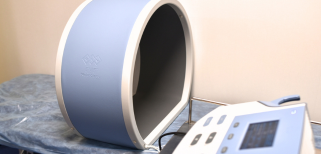

什麽是磁療? (by 運動表現物理治療) - more